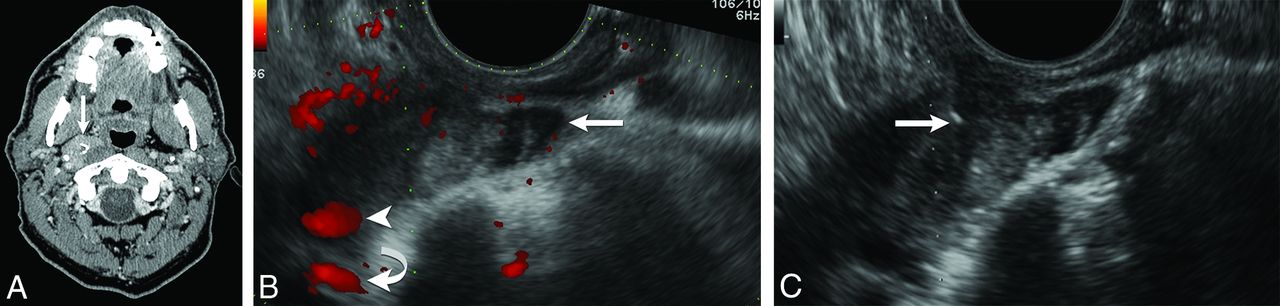

The needle was inserted through the guide and was directed transversely through the pharyngeal wall. The needle entered the sector FOV and appeared on the sonography image as a bright echogenic line. Visualization of the needle tip was critical to allow the operator to keep the needle tip at a safe distance from the internal carotid artery and internal jugular vein as the needle was guided along the planned path to the targeted mass (Fig 2). Cellular material was aspirated from the retropharyngeal mass by applying moderate (1–2 mL) continuous negative pressure for approximately 10 seconds with the needle tip kept within the targeted retropharyngeal mass.

Needle tip visualization. Transverse sonography during biopsy of a left retropharyngeal lesion demonstrates the needle and needle tip (white arrow) accurately placed within the lesion.